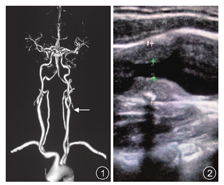

狭窄组120例中,40例经CTA检查确诊为颈动脉狭窄者,其中左侧20例,右侧20例,见图1;超声诊断80例颈动脉狭窄患者,其中左侧狭窄41例,右侧狭窄39例,见图2。按照狭窄程度不同,120患者进而分为轻、中、重度狭窄组3个亚组,分别为45例、30例、35例。